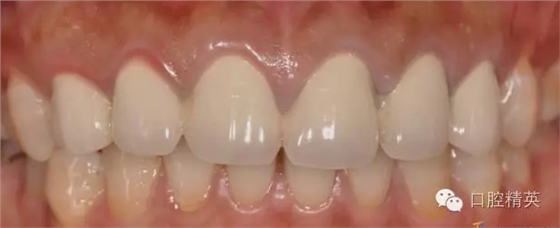

修復體完成后正面觀